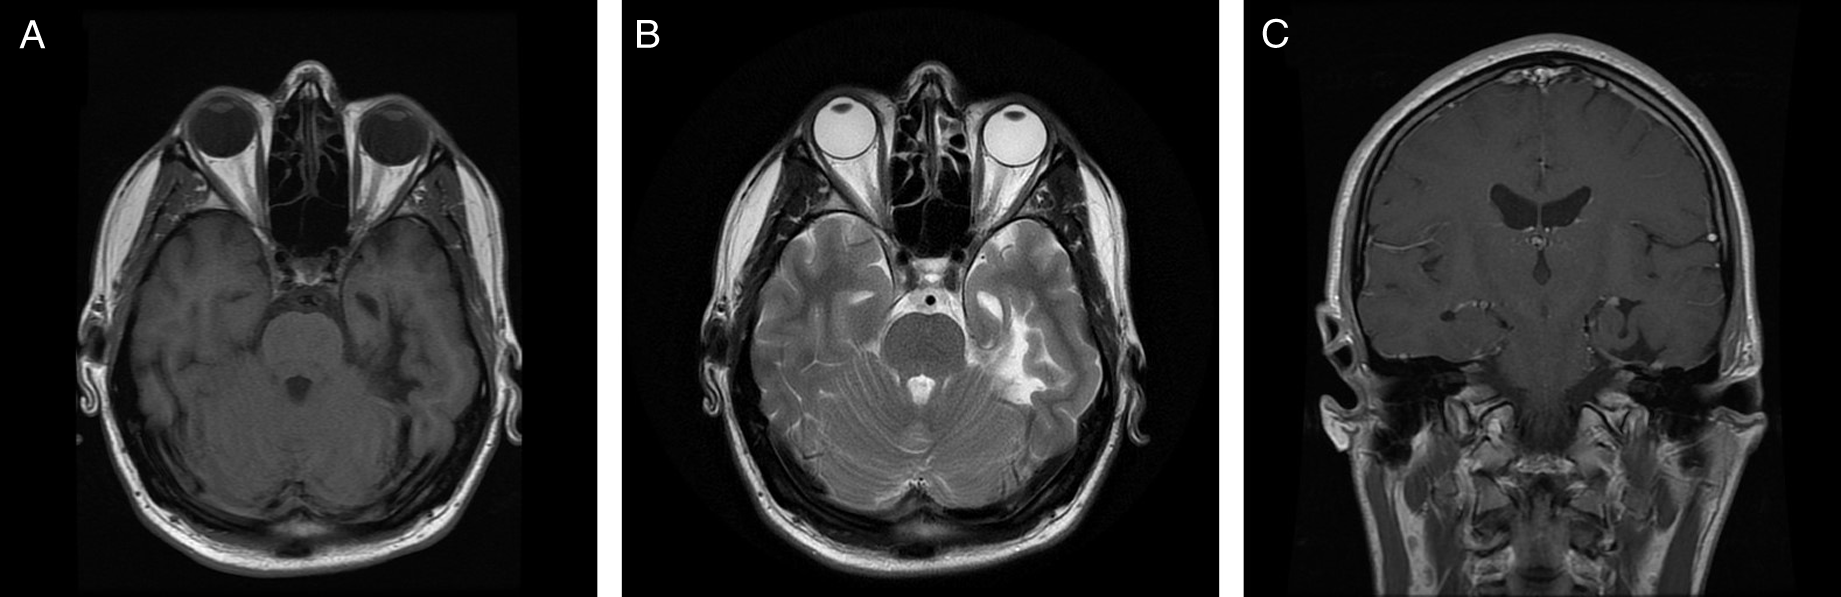

Magnetic resonance imaging of the brain revealed multiple abnormalities (Figure 1) including left mesial temporal encephalomalacia and T2-weighted imaging hyperintensities scattered throughout the supratentorial white matter. There was no abnormal enhancement.

Figure 1: Neuroimaging findings. Axial T1-weighted image (A), axial T2-weighted image (B), and coronal T1-weighted image with gadolinium (C) demonstrate left mesial temporal encephalomalacia and atrophy.

Classically, there is no identifiable underlying pathology of HC; however, increasing numbers of symptomatic cases have been reported. Head trauma is a rare cause of HC, and this represents the first case due to a temporal lobe lesion. Such cases have been referred to as ‘secondary HC’ in the literature Reference Prakash, Shah and Soni3,Reference Prakash and Patel4 ; however, a more accurate diagnosis in accordance with The International Classification of Headache Disorders, 3rd edition (ICHD-3) is persistent headache attributed to moderate or severe traumatic injury to the head with clinical features consistent with HC. 5 While the relationship between TBI and onset of headache with features of HC may be spurious, the temporal relation in this case suggests causation. The authors hypothesize that the connections between the mesial temporal lobe and the posterior hypothalamus were disrupted, resulting in clinical HC.